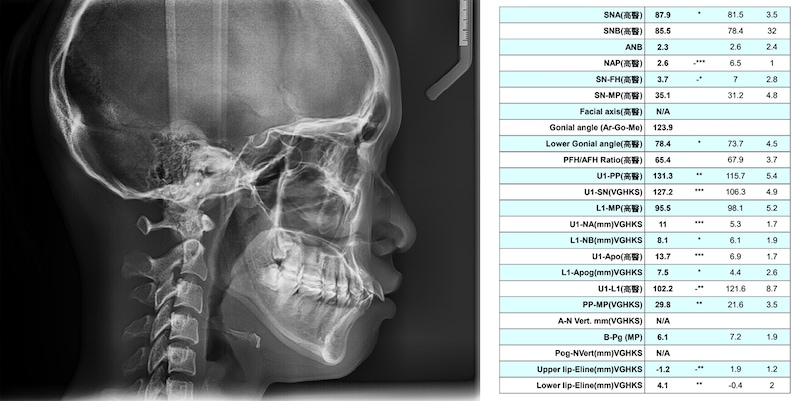

齒性暴牙

齒性暴牙相較於骨性暴牙單純許多。如下面案例,輪廓看起來暴暴的,但實際測量後AB數值正常,所以暴的原因單純是因為上前牙往前飛,這樣的案例在A點跟B點不錯的狀況下,不需要太多後退量就可以改善這個暴的感覺。